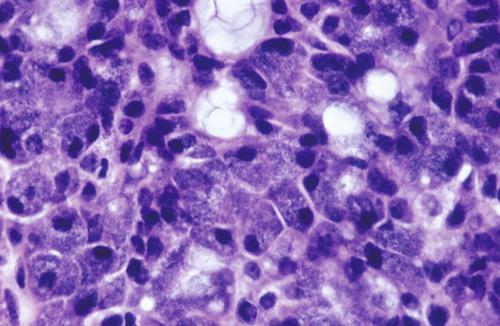

High-power view of epithelial lining showing double row of oncocytes with adjacent lymphoid stroma. The inner luminal layer consists of tall columnar cells with centrally placed, palisaded, and slightly hyperchromatic nuclei. Beneath this is a second layer of cuboidal or polygonal cells with more vesicular nuclei.

Warthin tumor